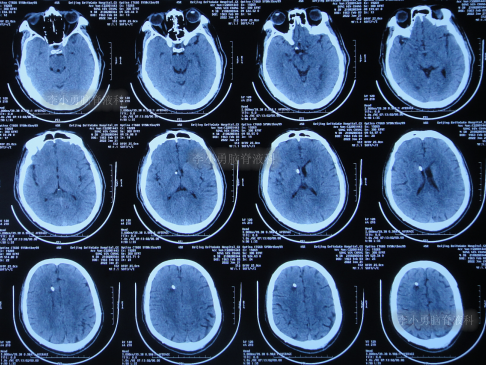

因脑脊液化验一直不正常,家属要求继续治疗,2月后脑脊液变正常,于2021年1月10日,进行了脑室腹腔分流术(图-14)。

图-14:2022年1月10日头颅CT

2022年1月25日(脑室腹腔分流术后15天)治好出院,出院时:神清气爽,走路完全正常(图-15);出院时头颅CT无异常(图-16)。

图-16:出院时头颅CT